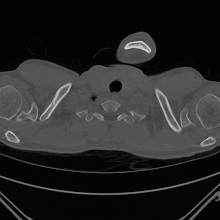

Le scanner thoracique permet de faire le bilan des blebs et des bulles des 2 poumons, de dépister une éventuelle tumeur pulmonaire et de connaître l’état du poumon sous-jacent.